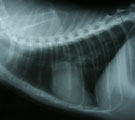

第7病日胸部X線所見。心房拡大すなわち「へたつきどんぐり状」の心陰影を呈し、心筋症が示唆された。 第16病日、カラードプラにて腹大動脈に血流途絶と逆流がみられ、剖検で同部位に血栓が認められた。 同病日の腹部エコー十二指腸横断面。背側の部分的層構造消失とその直下の不整形低エコー領域がみられた。 同病日の剖検所見。腹腔動脈分枝に鞍状血栓あり、膵右葉および十二指腸の部分的壊死がみられた(黒↑)。

経過:受診時、体温:36.0 ℃ 心拍数:140/分 呼吸数:42。可視粘膜蒼白、内股動脈圧低下しショック状態であった。意識レベルは低下し、伏臥のまま動かなかった。CBCおよび血液生化学検査にてPCV39%、白血球の増加(21500/μL)、肝酵素の上昇と黄疸(GPT232IU/L, GOT225IU/L, TBIL1.8mg/dl)、および著しい低カリウム血症(K1.6meq/L)を示した。胸部X線では心陰影拡大とびまん性間質陰影がみられた。腹部エコー検査にて総胆管拡張なく膵領域に特異所見なかったが上腹部走査時に激しい痛みを呈し十分な観察ができなかった。膵炎が疑われたが確定できなかった。オーナーの希望により、脱水補正、制吐、カリウム補正の対症療法を目的とする点滴通院治療となった。2日おきに3回行い次第に嘔吐がなくなり、次第にときおり起立して歩くようになった。第7病日の2度目の胸部X線撮影では心陰影は縮小していたが心房拡大所見みられ心筋症が示唆された。ところが、第14病日再び嘔吐し全身状態悪化し起立不能となり、混迷状態となった。血液検査にてPCV16%と減少し、血糖値が>600mg/dlと著しい上昇を示した。Kは2.9meq/Lと上昇していた。動脈血ガス分析では、pH7.33, Pco2 14mmHg, Po2 84 mmHg, [HCO3-] 7mmol/Lと過換気で代償された重度の代謝性アシドーシスを示した。糖尿病性ケトアシードーシスと診断した。やはり上腹部痛があり膵炎も関与している可能性もあった。入院にて、インスリンによる血糖管理、鎮痛、輸血、FOY持続投与、酸塩基電解質補正のための輸液を行った。2日目に血糖値は安定してきたが、両後肢の麻痺伸展、呼吸困難、嘔吐が継続してみられ、対症療法でコントロールできなかった。入院3日目、すなわち第16病日朝、激しい嘔吐のあと呼吸停止した。緊急気管内挿管し集中治療管理となった。挿管後も呼吸微弱であり機械換気による呼吸管理となった。管理中、0.1%ケタミン微量点滴を継続し、再度腹部エコー検査を行った。カラードプラにて腹部大動脈中央部に血流途絶と逆流が検出され、外腸骨動脈には血流が検知されなかった。さらに十二指腸横断面にて背側の部分的層構造消失とその直下の不整形低エコー領域がみられ膵炎が示唆された。人口呼吸管理を8時間続けたが自発呼吸発現せず、オーナー同意のもと機械換気を中止した。15分後心停止した。原因解明のため剖検することになった。十二指腸上部および膵右葉は腫脹し茶色に変色し周囲の腹腔内に茶褐色の腹水が少量貯留していた。十二指腸上部と膵右葉に供給する腹腔動脈分枝内に鞍状血栓がみつかった。また、腹大動脈の外腸骨動脈分岐部前4cmのところから前方に3cmの長さで血栓がみられた。腹腔動脈血栓塞栓による急性壊死性膵炎および大動脈血栓塞栓症と診断した。死因は急性壊死性膵炎によると考えられ、血栓は心筋症に関係するものと推定された。